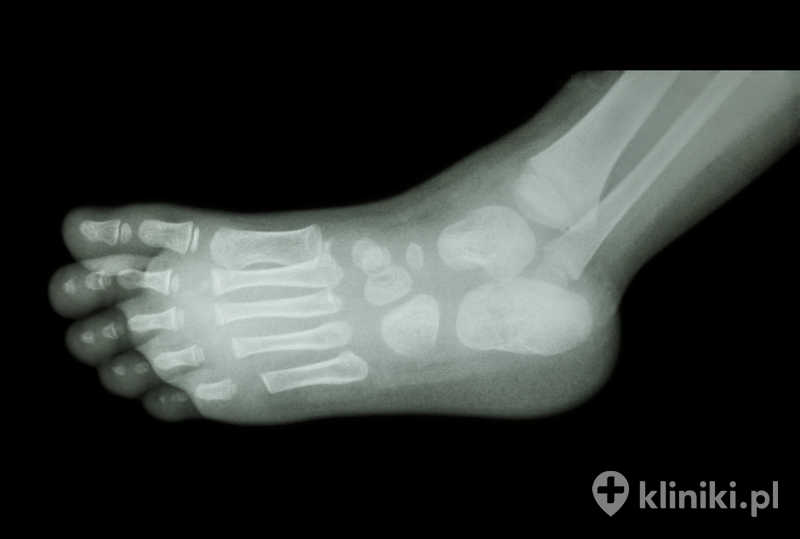

- badania obrazowe – rezonans magnetyczny, RTG, USG (jeśli zachodzi taka potrzeba).